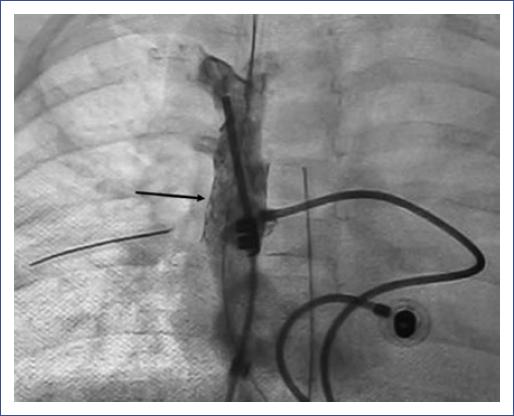

Mediante un cateterismo diagnóstico e intervencionista, se confirmó la obstrucción severa de la VCS mediante venografía (Fig. 2). Posteriormente, se realizó angioplastia secuencial en la VCS con catéter balón SterlingMR 6 x 20 mm, 8 x 20 mm hasta 14 atm en tres ocasiones. El procedimiento se repitió con balón MustangMR 12 x 20 mm, obteniendo un gradiente inicial de 27 mmHg y final de 15 mmHg, por lo que se decidió colocar stent Palmaz Génesis Trashepatic billar StentMR 10 x 17 mm, el cual se entregó en sitio de estenosis sin complicaciones y con gradiente final de 0 mmHg (Fig. 3).

Figura 3 Angiografía poscolocación del stent (flecha). Se observa paso libre del medio de contraste en la vena cava superior, llegando al atrio derecho, ventrículo derecho y tronco de la arteria pulmonar.

Los síntomas del paciente se resolvieron en las primeras 24-48 horas después de la colocación del stent. Por ecocardiografía, se confirmó la permeabilidad y ausencia de gradiente (Fig. 4). La paciente fue dada de alta con una evolución sin complicaciones.